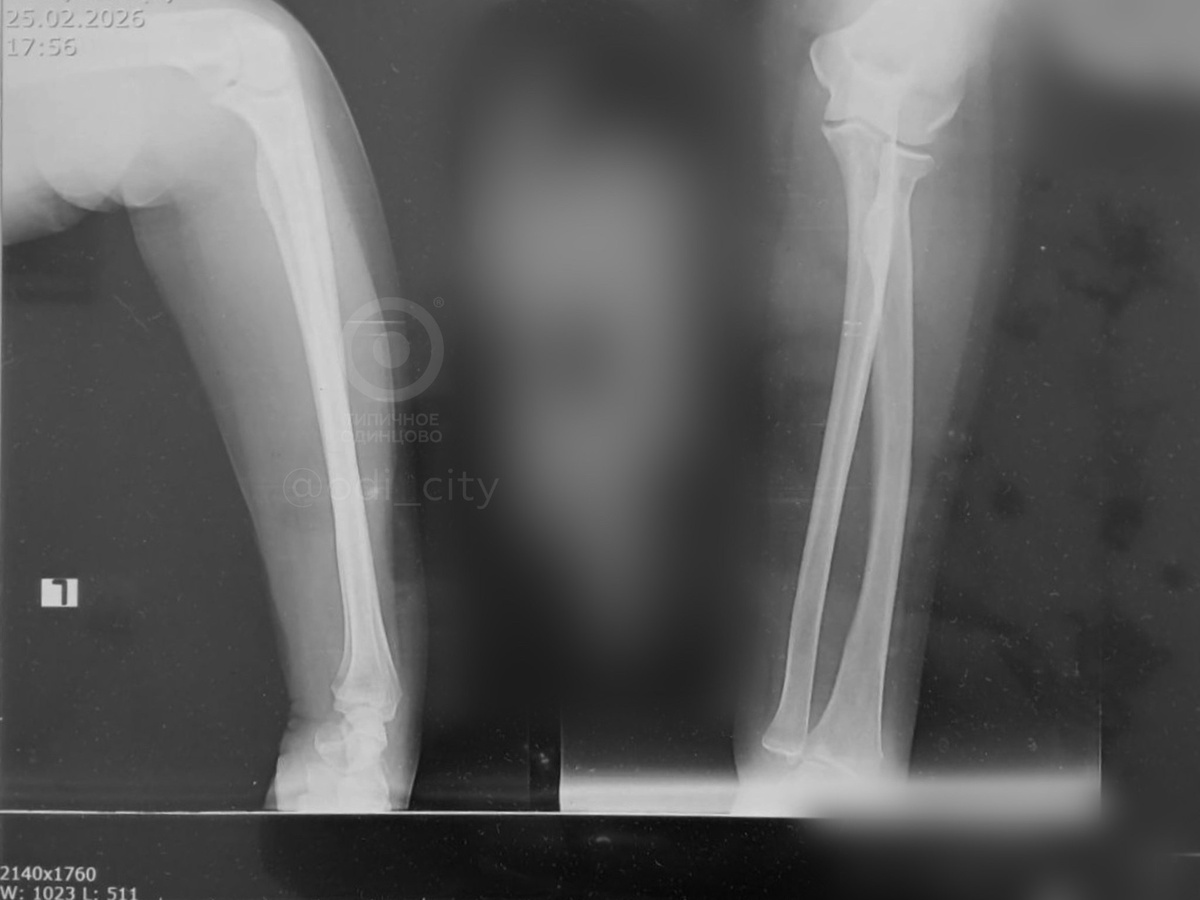

Пенсионерка сломала руку на выходе из поликлиники на Маршала Бирюзова: всему виной непочищенная от снега дорожка

Об инциденте рассказала подписчица «Типичное Одинцово». Публикуем ее рассказ: «Крик души. Территория центральной городской поликлиники г. Одинцово. Женщина пенсионер сходила к окулисту и при выходе из калитки упала и сломала себе руку. Да чтож это такое то. Неужели такой кусочек нельзя вычистить как следует. Сидят 2 здоровых лба, открывают шлагбаум машинкам. Даже не помогли ей встать. Стыд и позор». Источник: Открыть